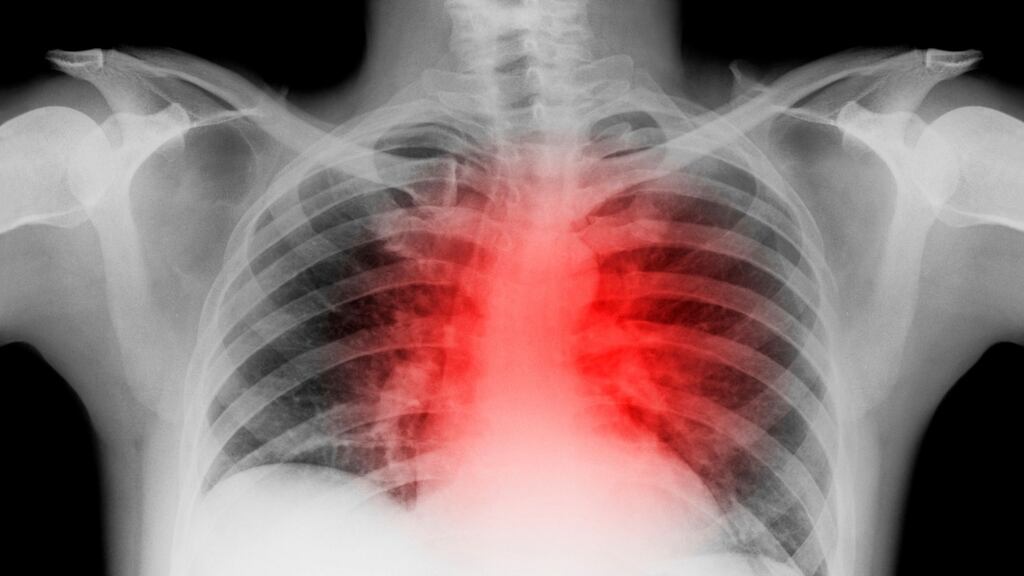

The risk of heart attack peaks at around 10pm on Christmas Eve, particularly for older and sicker people, according to a new study published in the British Medical Journal.

But by far the day with the highest risk was Christmas Eve, with a 37 per cent increased risk of heart attack, peaking at around 10pm.

The risk was greatest in the over 75s, and those with existing diabetes and heart disease, highlighting the need for society to raise awareness of this vulnerable group over the Christmas period, they added.